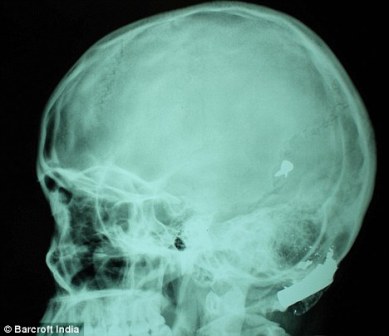

其中一顆子彈擊中她的左中耳,穿透了她的耳骨,然后擊中頭骨,嵌在了腦子里。另外兩顆子彈分別擊中她的右臂和心臟。印度Lok Nayak醫(yī)院的醫(yī)生稱,赫娜能夠康復(fù)完全是奇跡,她也足夠幸運。她的主治醫(yī)生稱:“當我們看到她的情況時,被嚇了一跳,幸運的是她活了下來!

這顆子彈沒有損壞大腦中控制身體機能的部分。盡管赫娜的手術(shù)很成功,但醫(yī)生表示,她還有出現(xiàn)感染和并發(fā)癥的可能。子彈毀掉了她的中耳,可能導致她耳聾。(楊柳)